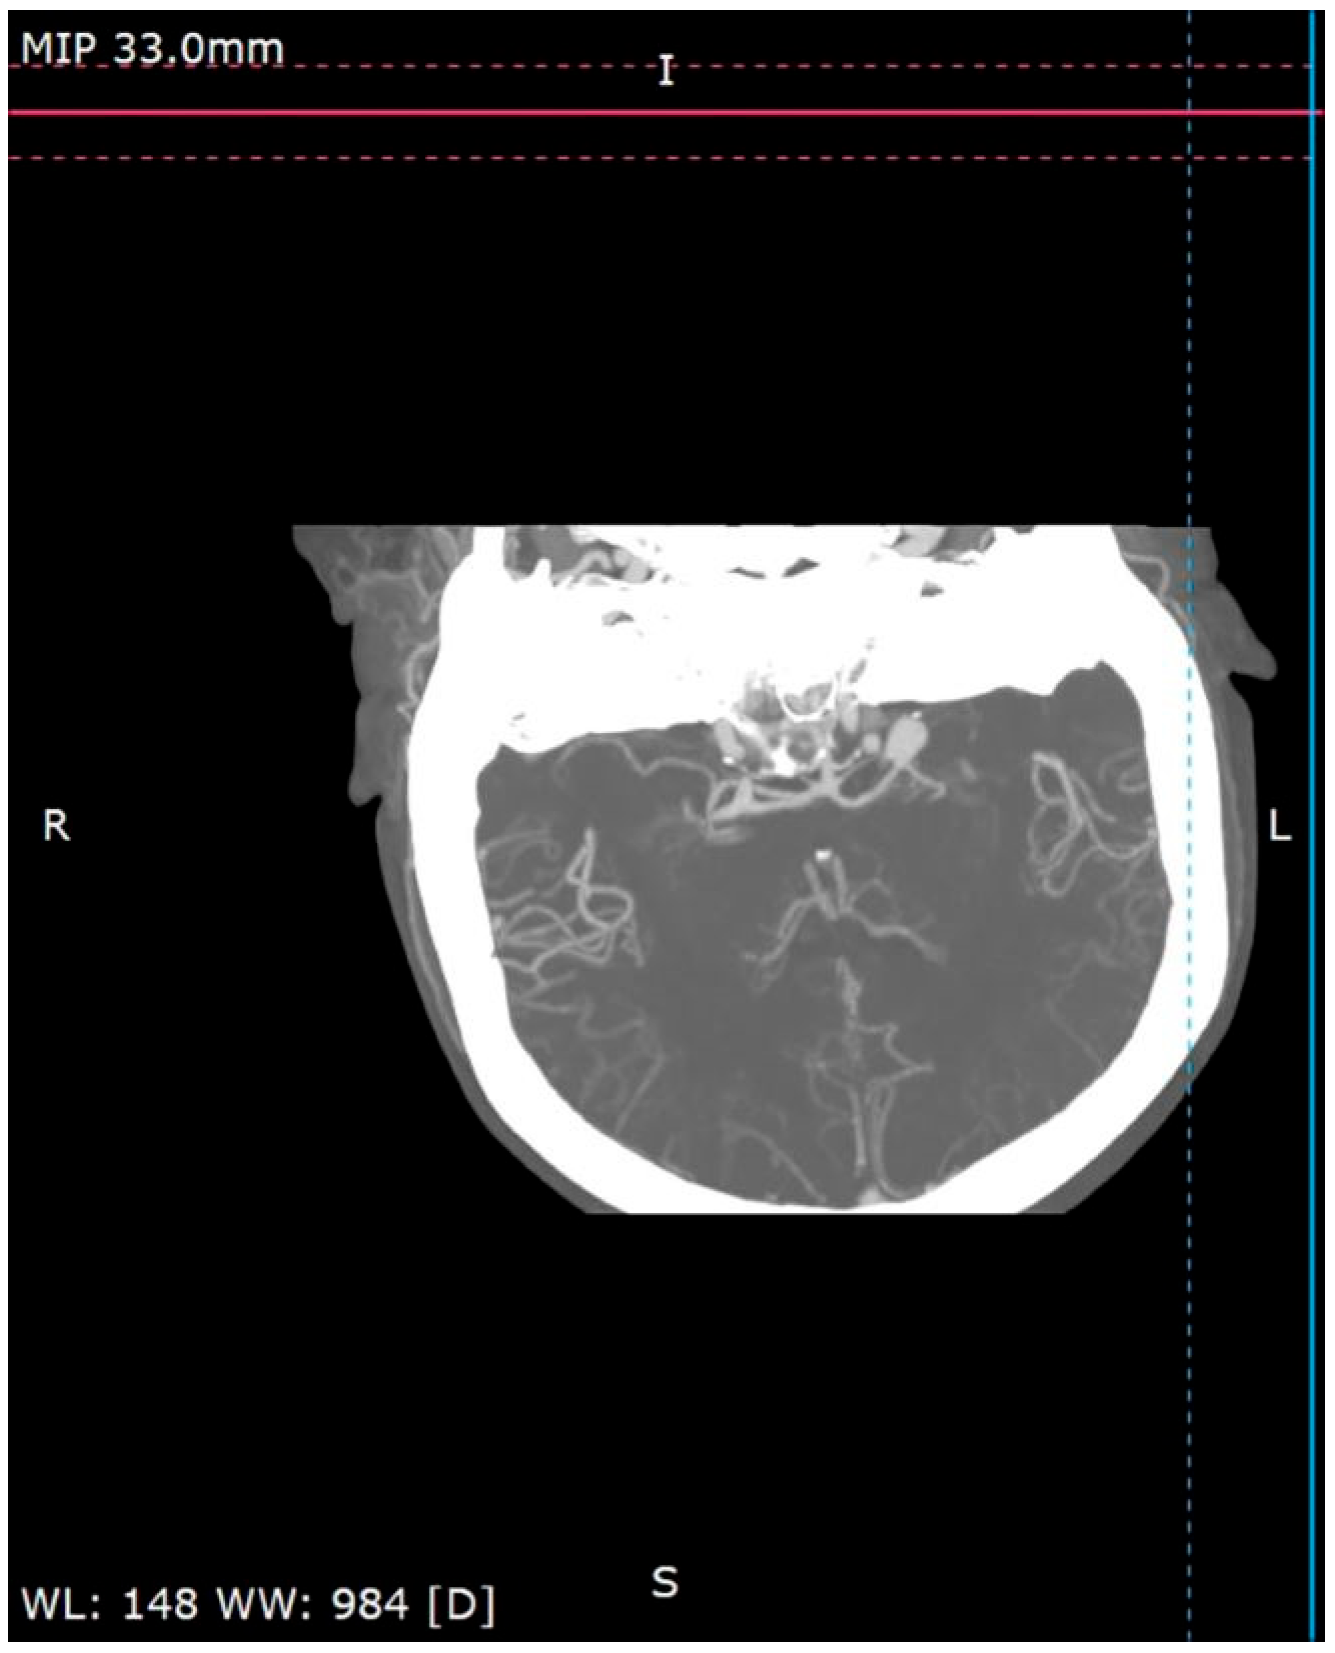

A 58-year-old woman treated for exudative pericarditis (effusion up to 6 mm) for the last 6 months was referred to a hepatologist/infectious diseases specialist with hypoechoic unclear lesions in the liver due to suspected hepatic tumor. Computed tomography confirmed simple hepatic cysts, while blood analysis revealed significant eosinophilia (23.4% in percentage, normal range 1–6%; eosinophil count: 1.45 in thousand eosinophils per microliter (K/μL), normal range 0.02–0.5 K/μL). The patient denied any symptoms, such as fever, abdominal pain, weight loss, cough or diarrhea in recent months; however, she described left-sided subjective eyeball enlargement, pain and redness. Her history included travels to Mexico, Egypt and Tunisia, as well as occasional raw meat consumption in Poland. She also had a dog, which did not receive regular parasite screenings and preventive medications. Her father had died from liver cancer. Lab tests confirmed the presence of IgG antibodies against Toxocara canis and sustained eosinophilia (18.1% in percentage, normal range 1–6%; eosinophil count: 1.01 in thousand eosinophils per microliter (K/μL), normal range 0.04–0.4 K/μL). Echinococcosis was excluded based on negative serology. Diagnosis of toxocariasis was further supported by clinical manifestations and exposure history with positive serology, and the patient was treated with mebendazole (200 mg twice a day for 5 days). Due to the suspicion of an ocular parasitic invasion, she was sent for an ophthalmological consultation. The ophthalmological examination was inconclusive, but head MRI revealed vascular abnormalities in brain arteries. CT angiography confirmed four aneurysms with one causing the constriction of an artery supplying the left eyeball (Figure 1, Figure 2 and Figure 3): two cerebral aneurysms of LICA (left internal carotid artery) size: 4.2 × 8.7 × 3.5 mm and 9.8 × 7.8 × 10.7 mm, one cerebral aneurysm of LMCA (left middle cerebral artery) size: 3.5 × 3.3 × 3.2 mm and the fourth enlargement for differentiation between an aneurysm and an infundibular dilations (3 mm) of LMCA. Clipping the aneurysms dissolved the ophthalmological problems. During the last check-up, normalization of the eosinophil count, full resolution of the ocular symptoms and no pericardial effusion were seen, further supporting our diagnosis of visceral toxocariasis. Hepatic cysts began to disappear. The patient was recommended to perform an abdominal ultrasound every 6 months.

Figure 3.

Cerebral CT angiography.